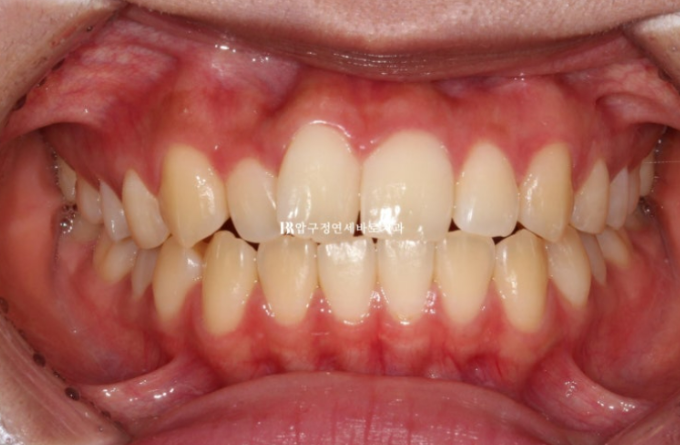

24.06

배열은 가지런해지고 앞니 교합도 처음에 비하여 깊어졌습니다.

유지장치까지 붙은 모습입니다.